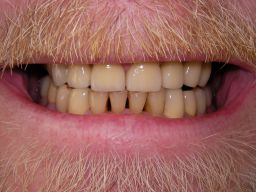

Besonderen Spaß macht mir großer, kombiniert festsitzend-herausnehmbarer Zahnersatz (sogenannter Kombi-Ersatz), auch mit Implantaten, weil er interessante Herausforderungen an den Behandler stellt. Diese Behandlungen sind oft langwierig, weil ein Behandlungsschritt auf dem anderen aufbaut: Häufig Parodontaltherapie, Wurzelkanalbehandlungen, Füllungstherapie, Implantate, erst am Ende Zahnersatz. Ob der Fall zur Zufriedenheit des Patienten gelöst werden konnte, stellt sich dann oft erst nach Monaten heraus. Hier ein einfacher Fall, bei dem keine besondere Vorbehandlung notwendig war. Der Patient, 58jährig, suchte die Praxis erstmals im September 2005 auf. Es erfolgten mehrere prothetische Planungen, der Gutachter des "Medizinischen Dienstes der Krankenkassen" (MDK) wurde noch von der Krankenkasse in Anspruch genommen, was heute bei größeren Planungen der Regelfall geworden ist. Umgesetzt wurde dann eine für einen solch großen Fall preisgünstige Lösung von 6434 Euro Gesamtkosten (4264 € Laborkosten, 2170 € Honorar). Die Krankenkasse übernahm als Festzuschuß 3843 €, für den Patienten verblieben 2591€. Im Januar 2006 ging es dann endlich los - zunächst allerdings beim Kieferchirurgen, weil wegen einer erhöhten, medikamentös bedingten Blutungsneigung es sicherer erschien, einige Zahnentfernungen von diesem durchführen zu lassen. Ausgangsbilder:

Hier das vorläufig letzte Bild dieses Falles mit maximaler Lippenöffnung einige Tage nach Eingliederung von Kronen und Prothesen bei der Nachkontrolle (Ende März 2006). Bislang lief, von einigen anfänglichen Prothesendruckstellen abgesehen, die aber leicht behoben werden konnten, alles glatt. Die Heiß-/Kaltempfindlichkeiten an den beschliffenen Zähnen, die häufig auftreten, waren nach der Zementierung der Kronen verschwunden. Die eigentliche prothetische Behandlung dauerte vom 22.2.06 bis zum 20.3.2006 (nur 5 Sitzungen), also 4 Wochen und war damit recht zügig. Ähnliche Fälle können auch 6 Wochen dauern.